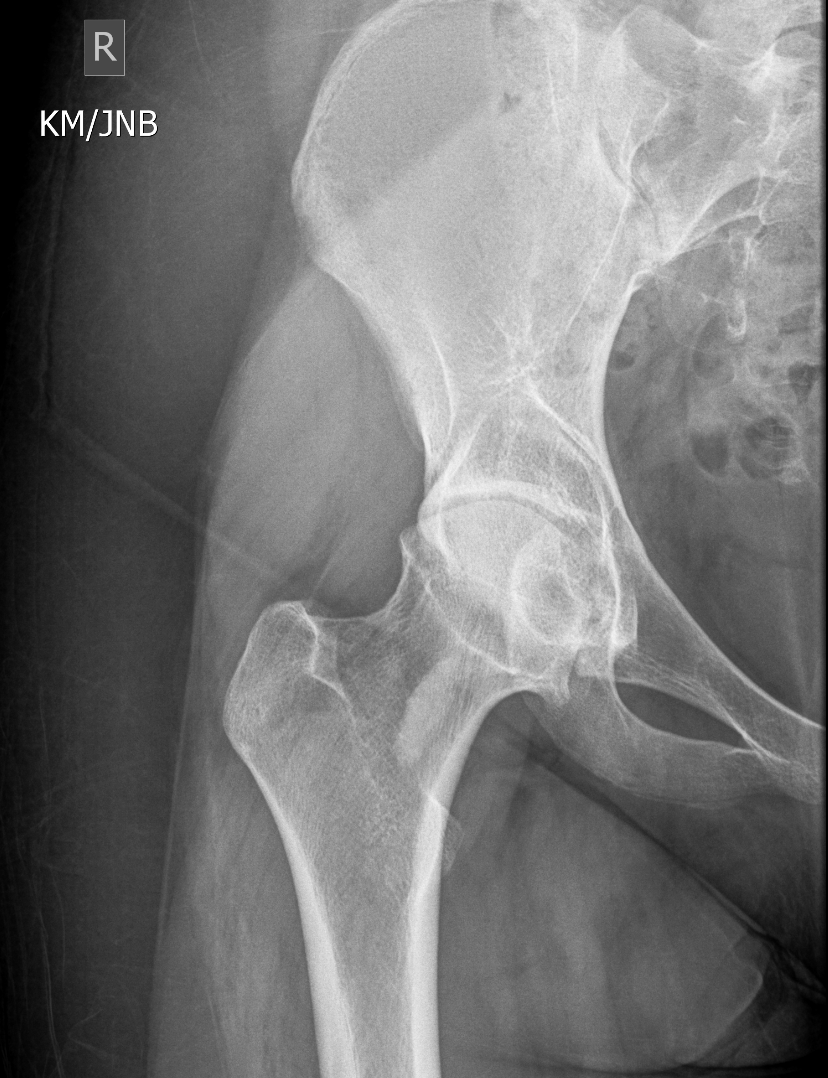

Section 1 Submit Findings CB1550 Findings Skeletal Survey - Technique Check Skull AP/Lat Yes No Cervical and Thoracolumbar spine Yes No Chest X-Ray Yes No Ribs – Left/Right Oblique Yes No Abdominal X-Ray Yes No Pelvis with both hips Yes No Bilateral Humerus, Forearm, Hand Yes No Bilateral Femur, Tibia/fibula, feet Yes No Any additional lateral views of the extremities Yes No The exam is over or under penetrated. Yes No The exam may or may not be limited by overlying structures or soft tissues, body habitus, patient positioning, support devices, or motion. Yes No The area of concern is indicated by the patient, technologist, or care provider. Yes No The area of concern is included on the exam. Yes No Soft Tissues There is soft tissue swelling, indistinctness of fat/muscle planes, gas, or laceration in the area of clinical concern. Yes No There is an effusion, fat pad displacement, or fat fluid level. Yes No There is a radiodense or lucent foreign body. Yes No There are other densities, calcifications, post-surgical changes, or support devices in the soft tissues. Yes No Any support lines/tubes. Yes No Bone There is a break or interruption of the continuity of the cortical or cancellous bone. Yes No There is overriding of the trabeculae with apparent sclerosis. Yes No There is displacement of a fracture fragment. Yes No There is bowing of the bone in addition to the fracture at the apex of the bowed bone concerning for the greenstick. Yes No There is a spiral fracture of the leg concerning for toddler’s fracture. Yes No There is abnormal angulation or bulging of the cortical surface relative to the normal cortex which could be from a buckle or torus fracture. Yes No There is a displaced fragment which may be from avulsion by a tendon, ligament, or joint capsule or from a comminuted or other fracture. Yes No The stress trabeculae or other trabeculae of the cancellous bone are interrupted or otherwise abnormal. Yes No There is subperiosteal or endosteal reaction which could indicate a healing or subacute fracture or other abnormality. Yes No There is hard/soft callus formation. Yes No There is remodeling of the bone. Yes No There is a corner fracture or metaphyseal lesion that could be from nonaccidental trauma. Yes No There are multiple fractures of different ages. Yes No There are vertebral body/spinous process fractures. Yes No There are rib fractures. Location - posterior or lateral. Yes No There is scapular/sternal fracture. Yes No There are fractures of the digits. Yes No There are wormian bones. Yes No There are intrasutural bones. Yes No There is metaphyseal abnormality (lucencies, increased density, erosion) which may be from something other than injury such as stress, metabolic disease (e.g. rickets with loss or distortion of the zone of the provisional calcification), neoplasm (e.g. leukemia), heavy metals, inflammation, or infection. Yes No There are metaphyseal spurs. Yes No There are bony deformities involving multiple bones. Yes No The bones are gracile. Yes No There are non-healing fractures. Yes No There is/are focal or multifocal lytic/lucent, blastic/sclerotic or mixed density lesion(s) or other abnormality. Yes No Overall bone density is increased or decreased with or without thinning or thickening of the cortical or cancellous bone. Yes No Growth plates, ossification centers, apophyses The growth plate(s) is/are abnormal. Yes No There is widening of the physis from a fracture with or without displacement of the epiphysis (Salter-Harris I). Yes No There is a fracture through the physis which then extends into the metaphysis with or without angulation or displacement (S-H II). Yes No There is a fracture through the physis which then extends into the epiphysis and is intra-articular, with or without angulation or displacement (S-H III). Yes No There is a fracture through the metaphysis, physis, and epiphysis which extends into the joint space with or without angulation or displacement (S-H IV). Yes No There is narrowing of the physis from a compression fracture (S-H V). Yes No The apophysis, epicondyle, secondary ossification center, or accessory ossicle is displaced or otherwise abnormal. Yes No The ossification centers are underdeveloped. Yes No Joints and alignment There is an effusion, fat pad displacement, or fat fluid level. Yes No The epiphysis or subchondral bone is fractured, interrupted, flattened, compressed, impacted, displaced, or otherwise abnormal. Yes No There is an intra-articular loose body or chondrocalcinosis. Yes No The joint is widened, narrowed, dislocated, malaligned, or incongruent. Yes No There is pseudoarthrosis. Yes No Other findings There are developmental changes or other anatomic variants or other existing conditions that may or may not be contributing to symptoms which can or should be further evaluated non-emergently or are otherwise incidental. Yes No The remainder of the exam is abnormal for age. Yes No The lungs show focal airspace opacity. Yes No There is pneumothorax. Yes No There is organomegaly. Yes No There is intra-abdominal calcification. Yes No There is displacement of the bowel loops. Yes No There is free intraperitoneal air. Yes No The bowel loops are dilated/obstructed. Yes No There is paraspinal soft tissue abnormality. Yes No